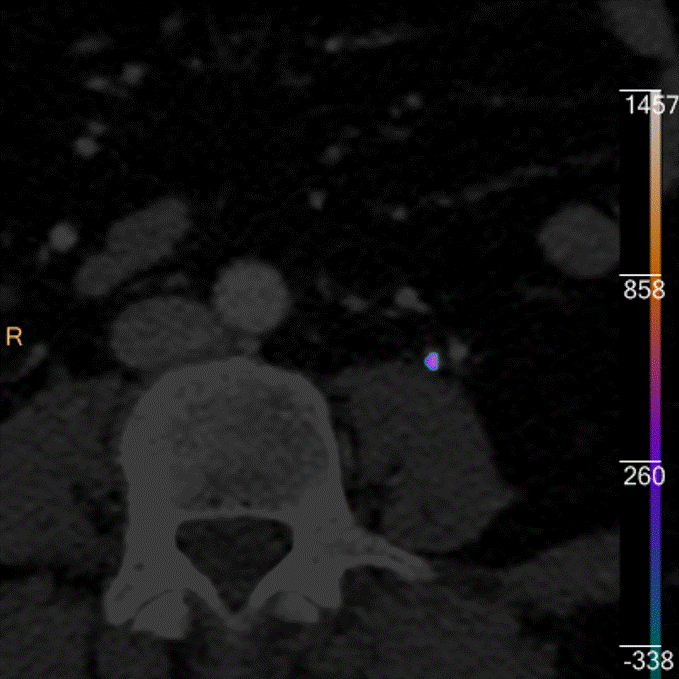

Something new for adrenal nodules